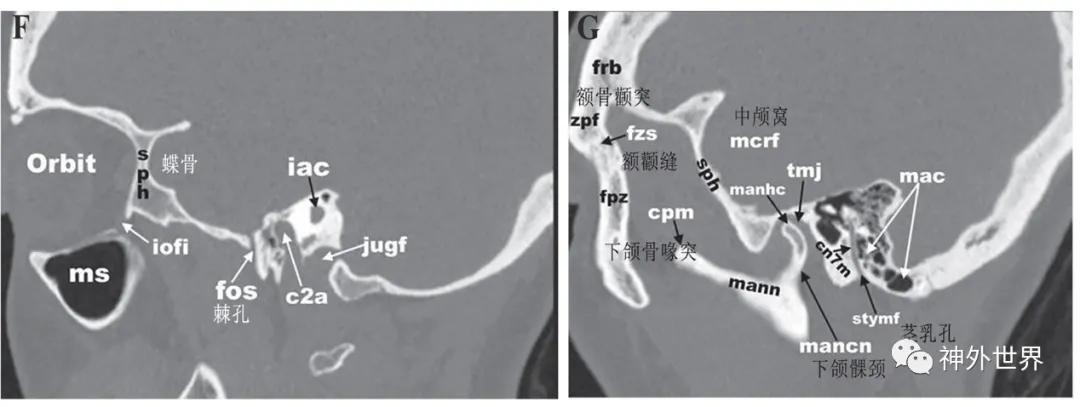

1.2颅底CT骨窗影像解剖

图3:颅底CT骨性横断面影像解剖

图4:颅底CT骨性冠状面影像解剖

图5:颅底CT骨性矢状面影像解剖